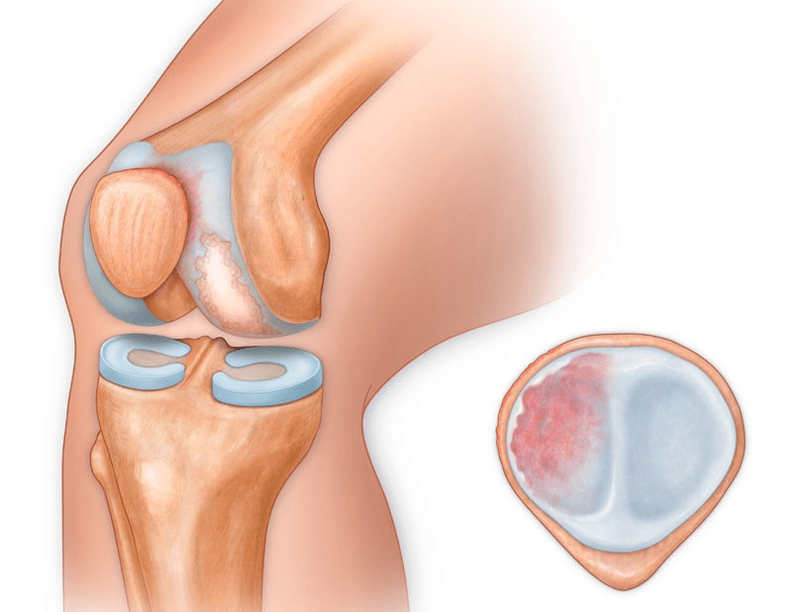

Outre la partie interne ou externe du genou, l'arthrose peut également affecter les surfaces situées entre la rotule et le sillon intercondylien du fémur. Cette option est appelée Arthrose fémoro-patellaire.

La cause est généralement une subluxation, une fracture ou une latéralisation de la rotule.

- Blessures (fractures, ménisque déchiré et ligament croisé antérieur). Malheureusement, ces blessures provoquent un stress excessif sur le cartilage chez chaque personne, quel que soit son âge. Une fracture d'une partie de l'os recouverte de cartilage s'accompagne de la formation d'une irrégularité - une « marche ». Dans cette zone, l'abrasion et l'arthrose surviennent avec le mouvement ;

- polyarthrite rhumatoïde, maladie de König (ostéochondrite disséquante), conséquences d'une inflammation purulente des articulations (gonite), etc.